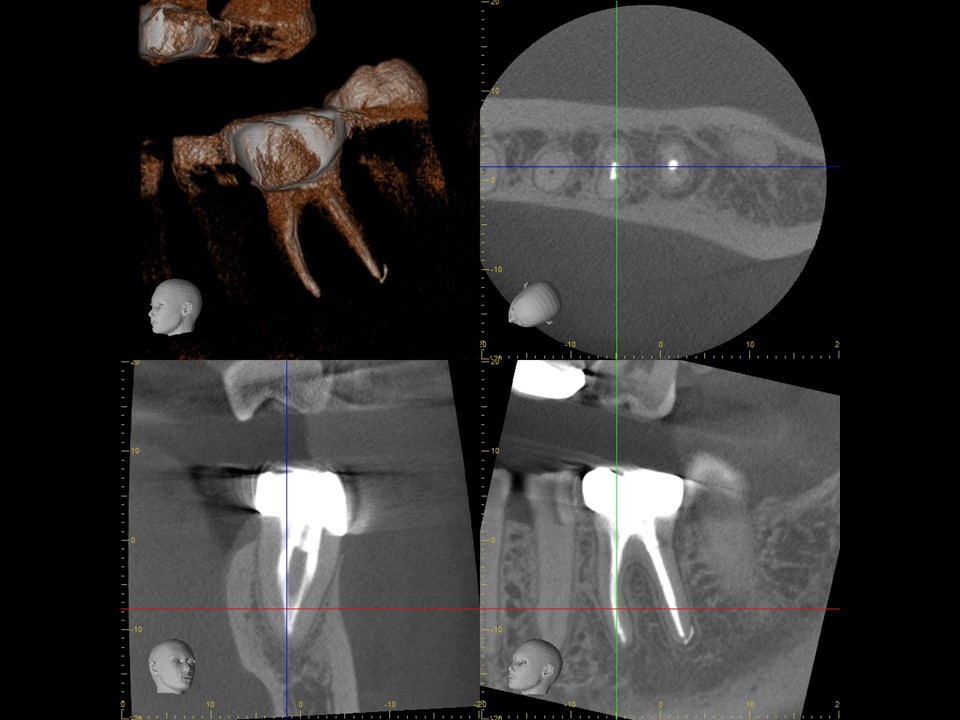

| 治療前レントゲン | 治療前CT |

|---|---|

| 治療前レントゲン |

|---|

| 治療前CT |

初診時レントゲンおよびCT画像です。根尖部には根尖病変と思われる黒いX線透過像を認めます(矢印)。

歯冠部には、歯髄に近接するレジン充填と思われる白いX線不透過像を認めます。深い虫歯治療後に歯髄壊死を生じたと推察されます。